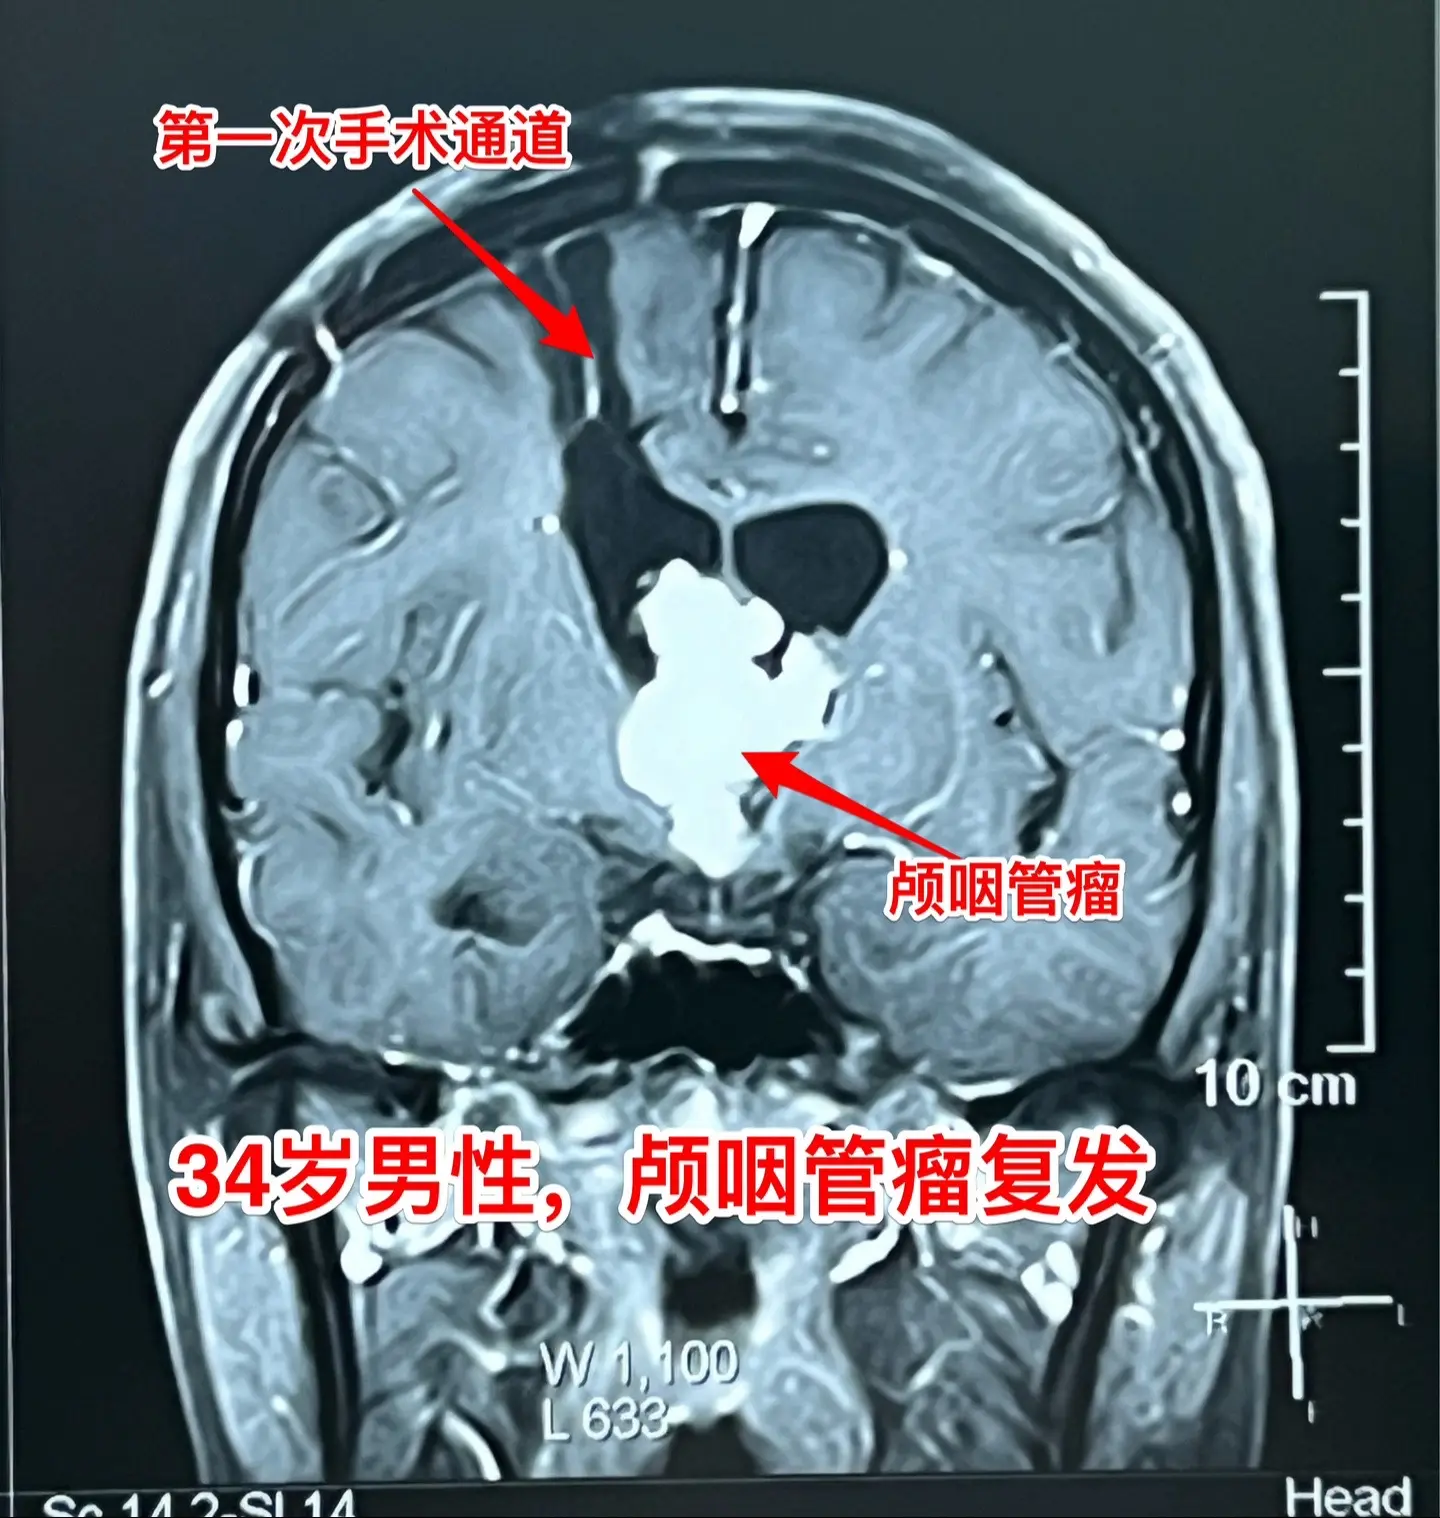

34岁广州男性颅咽管瘤复发。一年前他在广州市某医院行开颅手术切除颅咽管...